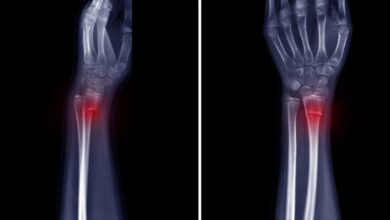

• الكسور (Fractures)

قال تعالى: (رَبَّنَا ٱغۡفِرۡ لِي وَلِوَٰلِدَيَّ وَلِلۡمُؤۡمِنِينَ يَوۡمَ يَقُومُ ٱلۡحِسَابُ) ما هو الكسر؟ الكسر هو انقطاع أو شق يحدث في العظم…